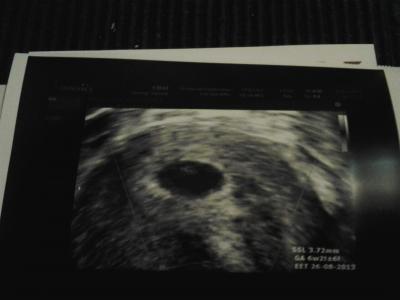

Hey habe es heute doch noch Geschäft einen Fa Termin zu bekommen, habe auch meinen mutterpass bekommen und neues Foto Termin auf 17.1 das ist zum Glück nicht so lange :-) und man konnte heute das Herzchen bubbern sehen, jetzt bin ich wesentlich entspannter und Termin soll sein 22.8 aber laut US 26.8 :-) aber egal Hauptsache ich. Bleibe bei euch :-)

Bild zu :-) fa bericht + foto - Forum für August - Mamis

Herzlichen Glückwunsch! Ein schönes Bild von deinen Krümel